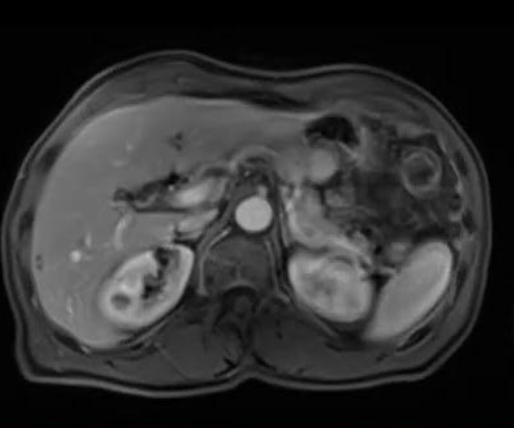

CAZ nr 119: Imagistica CT și IRM la un pacient cu tumoră stromală gastro-intestinală (GIST)

Video 3: achiziție IRM axial T2

Discuţie caz nr 119: pacientul efectuează CT în vederea operației pentru defect de perete abdominal anterior și se evidențiază o leziune expansivă în spațiul gastro-hepatic care este hipodensă nativ comparativ cu parenchimul hepatic și care este izodensă cu parenchimul hepatic în tip arterial, venos și tardiv. Pacientul este trimis la IRM pentru caracterizare tisulară suplimentară și se remarcă că leziunea este în hipersemnal T2, hiposemnal T1 comparativ cu parenchimul hepatic, prezintă priză de contrast, este în contact cu faţa viscerală a lobului stâng hepatic și se continuă cu peretele gastric la nivelul antrului – suspiciunea este de GIST.